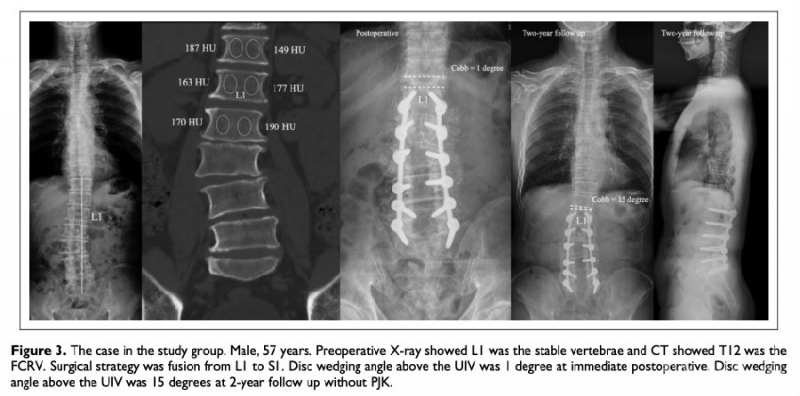

临床意义:退变性腰椎侧弯术后冠状位失衡与上端固定椎的选择密切相关。站立时间长短、透照角度对X线水平椎、稳定椎、中立椎的判断造成影响。我们提出冠状位第一反转椎(First coronal reverse vertebrae, FCRV)的概念,定义为与主弯范围内椎体凹凸侧骨密度(以CT值代表)分布相反的近端第一个椎体,FCRV与FCRV-1椎间盘剪切力大,理论上当UIV位于FCRV以下时,UIV与FCRV之间应力集中可能加速术后ASD发生。本研究目的在于分析上端固定椎位于冠状位第一反转椎以上是否可降低退变性侧弯患者术后近端邻近节段退变的风险。

材料与方法:回顾性分析116例退变性侧弯患者的临床及影像学数据,根据ASD的发生情况分为2组:研究组(ASD阳性组)和对照组(ASD阴性组)。测量腰椎椎体整体松质骨HU值和椎体凸侧和凹侧松质骨HU值。测量方法:选择椎体前皮质骨后方2mm、椎体中部、椎体后皮质骨前方2mm三个层面,上述三个层面测量值的平均值为最终椎体HU。

结果:12例患者的FCRV位于稳定椎近端第2个椎体,32例患者的FCRV位于稳定椎近端第1个椎体,35例患者的FCRV位于稳定椎,23例患者的FCRV位于稳定椎远端第1个椎体,14例患者的FCRV位于稳定椎远端第2个椎体。当UIV位于FCRV近端时,无患者出现ASD,而当UIV位于FCRV时,15.4%的患者出现ASD。在研究组中,当UIV位于FCRV时,1例患者(3.9%)出现近端侧弯进展,当UIV位于FCRV远端时,17例患者(29.8%)出现近端侧弯进展。

结论:冠状位第一反转椎远端椎间盘是冠状面应力集中点,上端固定椎位于冠状位第一反转椎之上,术后近端邻近节段退变发生率低。冠状位第一反转椎的判定比稳定椎更可靠,在上端固定椎选择上更有参考价值。

图注1:UIV位于FCRV远端时,术后2年近端邻近节段Cobb角椎间增大